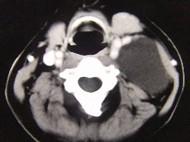

问题 男性,40岁,颈部出现无痛性囊性包块2年余,CT扫描如图所示,最可能诊断为()

选项 A.淋巴管瘤 B.血管瘤 C.淋巴结肿大 D.神经源性肿瘤 E.颈动脉鞘瘤

答案 A